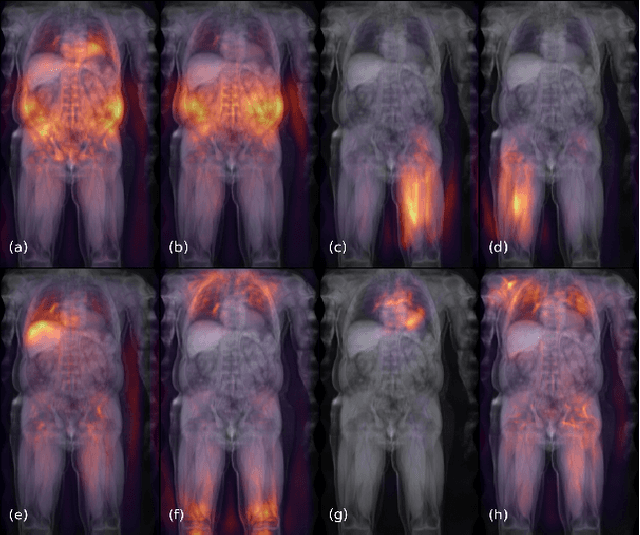

Abstract:Large-scale medical studies such as the UK Biobank examine thousands of volunteer participants with medical imaging techniques. Combined with the vast amount of collected metadata, anatomical information from these images has the potential for medical analyses at unprecedented scale. However, their evaluation often requires manual input and long processing times, limiting the amount of reference values for biomarkers and other measurements available for research. Recent approaches with convolutional neural networks for regression can perform these evaluations automatically. On magnetic resonance imaging (MRI) data of more than 40,000 UK Biobank subjects, these systems can estimate human age, body composition and more. This style of analysis is almost entirely data-driven and no manual intervention or guidance with manually segmented ground truth images is required. The networks often closely emulate the reference method that provided their training data and can reach levels of agreement comparable to the expected variability between established medical gold standard techniques. The risk of silent failure can be individually quantified by predictive uncertainty obtained from a mean-variance criterion and ensembling. Saliency analysis furthermore enables an interpretation of the underlying relevant image features and showed that the networks learned to correctly target specific organs, limbs, and regions of interest.

Abstract:Purpose: To enable fast and automated analysis of body composition from UK Biobank MRI with accurate estimates of individual measurement errors. Methods: In an ongoing large-scale imaging study the UK Biobank has acquired MRI of over 40,000 men and women aged 44-82. Phenotypes derived from these images, such as body composition, can reveal new links between genetics, cardiovascular disease, and metabolic conditions. In this retrospective study, neural networks were trained to provide six measurements of body composition from UK Biobank neck-to-knee body MRI. A ResNet50 architecture can automatically predict these values by image-based regression, but may also produce erroneous outliers. Predictive uncertainty, which could identify these failure cases, was therefore modeled with a mean-variance loss and ensembling. Its estimates of individual prediction errors were evaluated in cross-validation on over 8,000 subjects, tested on another 1,000 cases, and finally applied for inference. Results: Relative measurement errors below 5\% were achieved on all but one target, for intra-class correlation coefficients (ICC) above 0.97 both in validation and testing. Both mean-variance loss and ensembling yielded improvements and provided uncertainty estimates that highlighted some of the worst outlier predictions. Combined, they reached the highest quality, but also exhibited a consistent bias towards high uncertainty in heavyweight subjects. Conclusion: Mean-variance regression and ensembling provided complementary benefits for automated body composition measurements from UK Biobank MRI, reaching high speed and accuracy. These values were inferred for the entire cohort, with uncertainty estimates that can approximate the measurement errors and identify some of the worst outliers automatically.